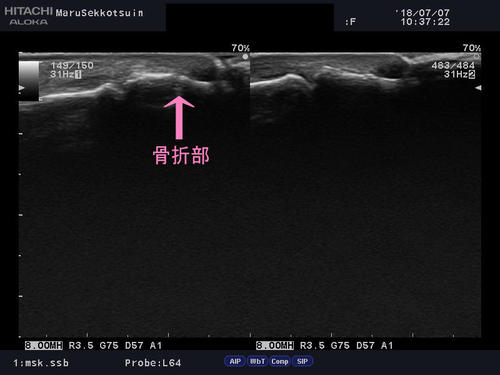

家の壁に、誤って足を突いちゃったら骨折しちゃった・・・

基節骨骨折.jpg